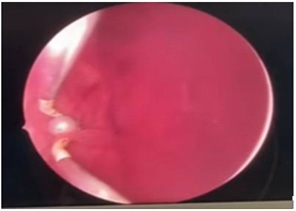

Cystoscopy was done to detect mucosa lesions in bladder; the whole mucosa was congested and red. There were multiple hemorrhagic areas in whole bladder mucosa; it was bled on touch. There was no focal ulcer or tumor. Therefore, generalized congested mucosa, hemorrhagic areas were probably due to DIC or CMV cystitis or candida cystitis or bacteria cystitis. The color of urine coming from Vescio-ureteric orifice of graft kidney was clear. Hemostasis was done with Ball electrode; bladder wash out was done with Tomey’s glass syringe. Figure 9-15 reveal cystoscopy findings. Abdominal tomogram was done; it revealed a swollen allograft kidney with air in the renal pelvis and renal vessels and subcapsular area suggestive of emphysematous allograft pyelonephritis. And, air along bladder wall was seen indicating emphysematous cystitis. They are illustrated in (Figure 16-19).